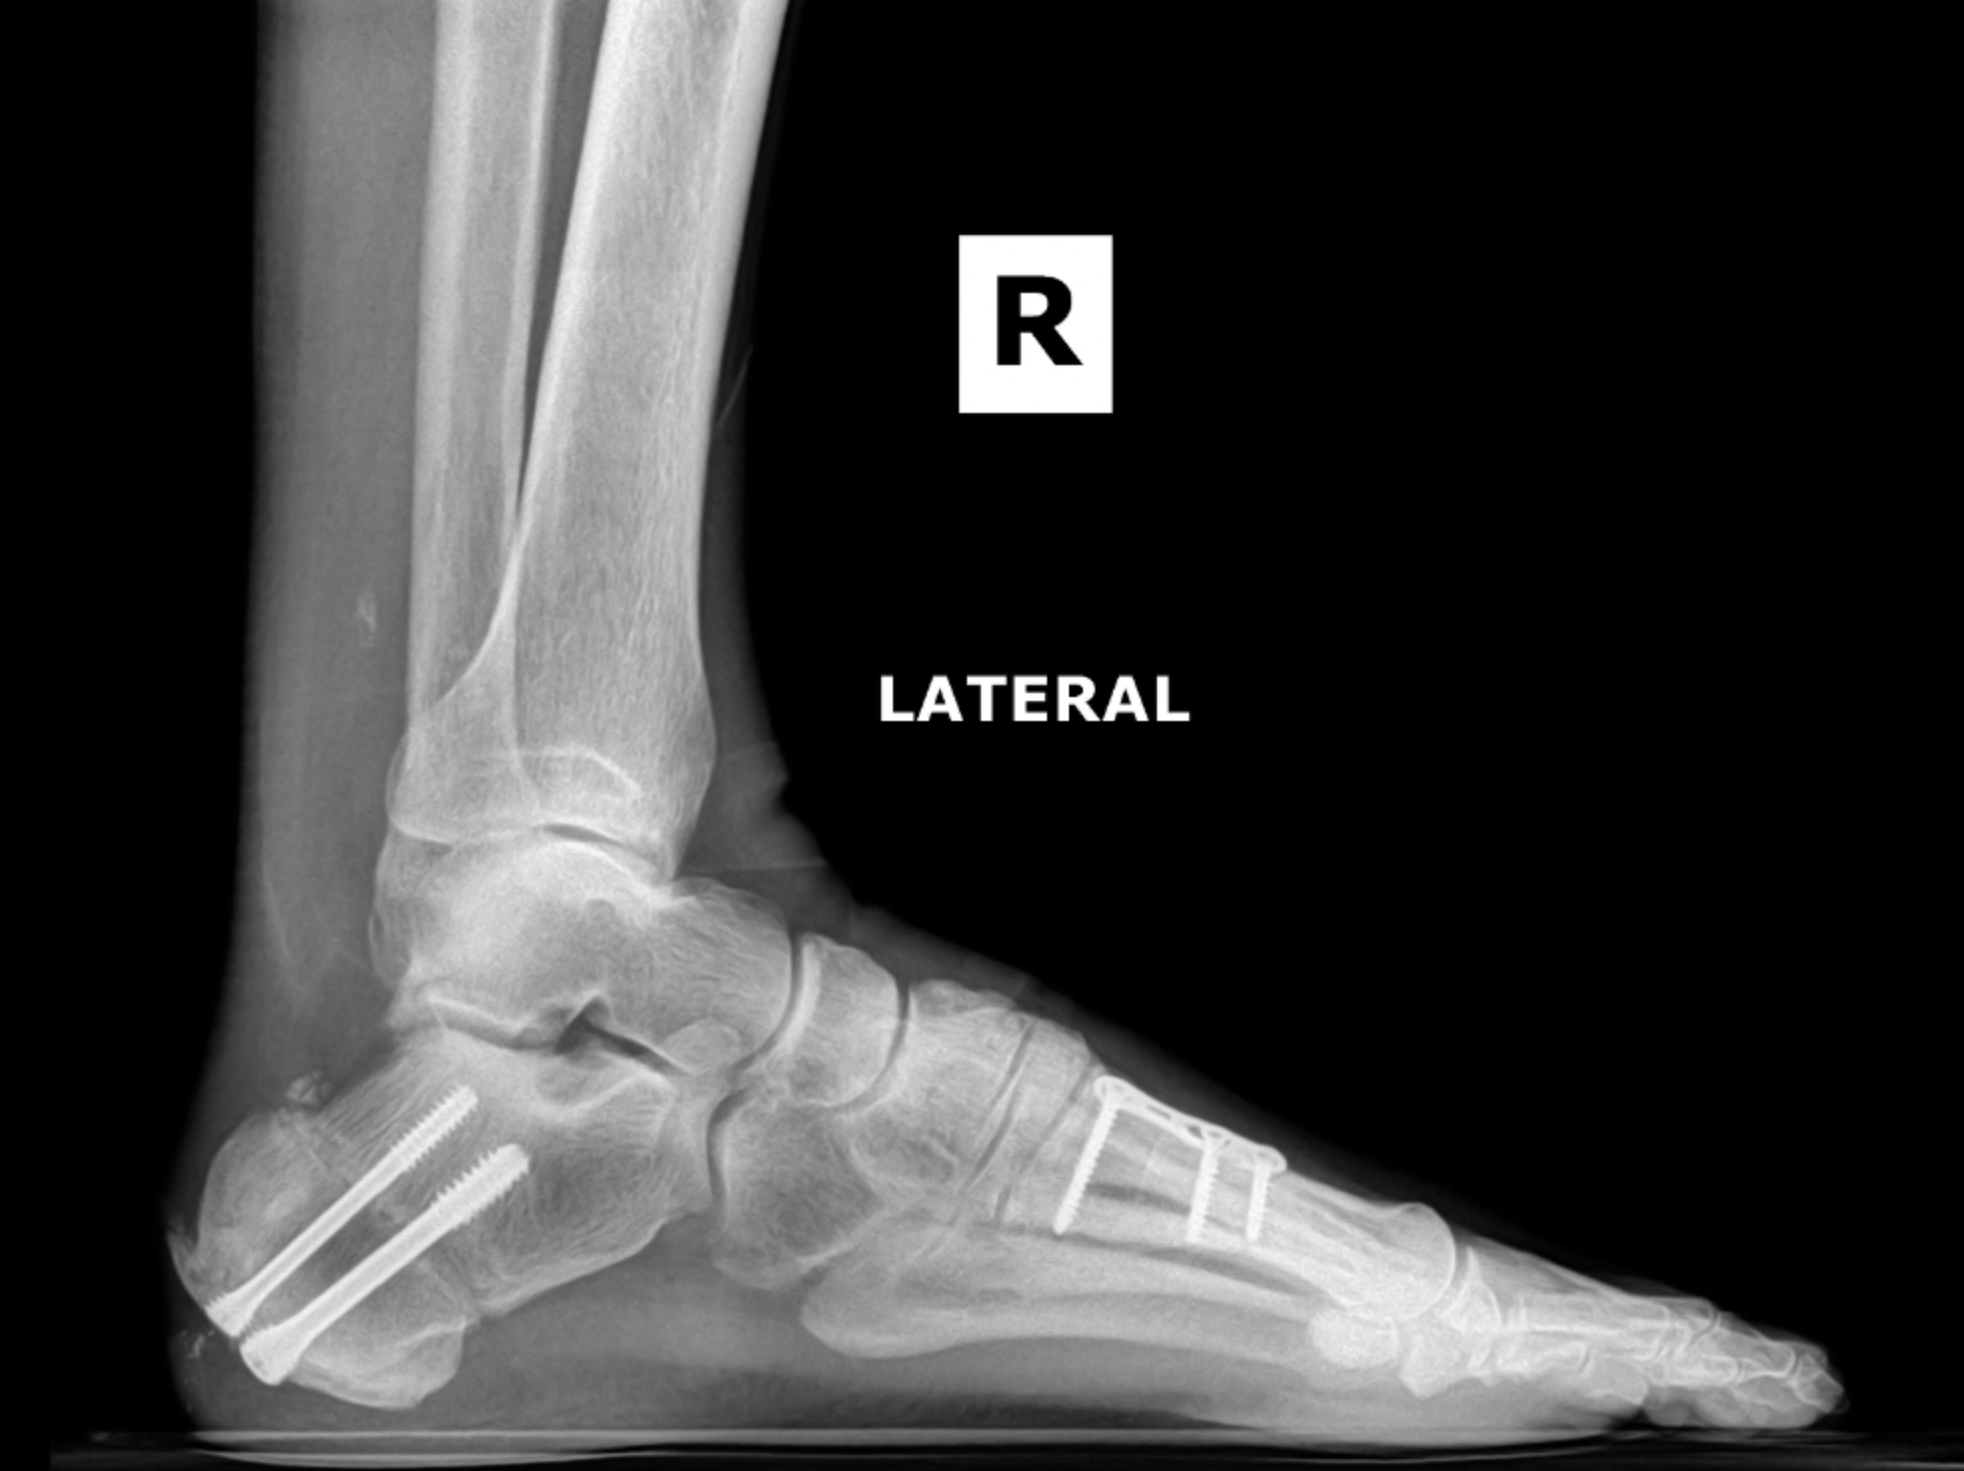

Postop XR Images